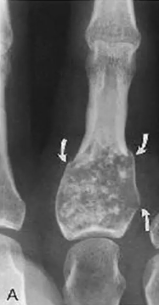

Enchondrome : Bénin et ASX, sauf si trauma (fx patho) mais peut devenir malin

- Lésion expansible dans les phalanges

- PAS colonne

- 10-30 ans

- Lésion lytique, « popcorn calcification »

- Enchondrome Multiple = ollier’s desease